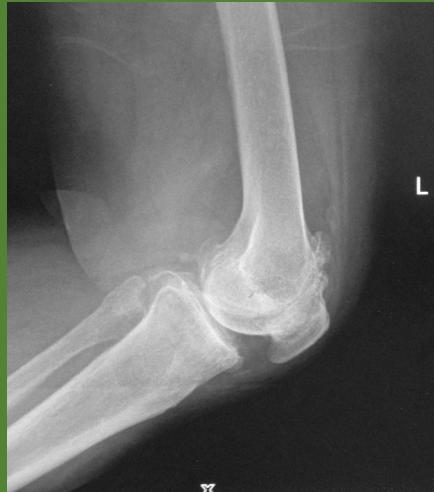

| Compartment Syndrome | Increased pressure within a closed fascial compartment, leading to reduced tissue perfusion, hypoxia, and irreversible muscle and nerve damage. Causes: Fractures (especially tibia/forearm), severe soft tissue trauma, arterial injury, burns, tight casts/dressings, post-ischemic reperfusion swelling, IV fluid extravasation, and bleeding disorders (e.g., hemophilia). High-Risk Notes: Pain may be absent in altered consciousness, children (monitor analgesia response), polytrauma, sedated/epidural cases, or concomitant nerve damage. Open fractures do not always decompress pressure. Gross/Clinical: -tense, shiny leg swelling with blisters in compartment syndrome.Imaging: - Intraoperative fasciotomy | History/Symptoms: Pain out of proportion to the injury (e.g., a “bursting” sensation), which is not relieved by analgesia. Clinical Features (The 5 P’s): - Pain with passive stretch (early, key sign; e.g., ankle dorsiflexion for leg, wrist for forearm). - Paresthesia (early). - Palpable tense swelling (shiny skin, blisters: clear=mild, serosanguinous=severe, bloody=worst; dusky/pallor skin). - Pallor, Paralysis, Pulselessness (late, ominous signs; pulses often palpable until late). Investigations: Primarily a clinical diagnosis (high suspicion key). Compartment pressure measurement can confirm: absolute pressure >30 mmHg or Delta Pressure (Diastolic BP - Compartment P) ≤ 25 mmHg. | Initial: ABCs, supplemental oxygen. Remove all circumferential dressings, casts (bivalve to skin), and splints. Elevate the limb to heart level (not above; higher reduces inflow). Correct any hypotension. Surgical: Urgent Fasciotomy if no response within 1h or confirmed pressure (prophylactic in high-risk like major osteotomy). Release all compartments/skin with long incisions; debride necrotic muscle via 4C’s (early: pink/red, soft, contracts/bleeds on pinch; late: dark, firm, no response); preserve neurovascular. Wound open (bulky dressing/splint, VAC, or boot-lace gradual closure); repeated inspections x48h; coverage in 3-5 days (skin graft usual; flap if nerves/vessels/bone exposed). | Cellulitis, Deep Vein Thrombosis (DVT), Arterial occlusion, Severe soft tissue injury without compartment syndrome; equivocal cases in polytrauma. | Complications: Volkmann’s ischemic contracture (permanent deformity, weakness, sensory loss, chronic pain). Contraindications (Fasciotomy): Confirmed >48h (irreversible damage, high infection risk from dead tissue); crush injuries with already necrotic muscle. |

| Open Fracture | A fracture with a breach in the overlying skin and soft tissues, creating communication with the external environment. All open fractures are considered contaminated (even small punctures; aka compound fracture). Causes: Can result from high-energy trauma (RTAs, falls, firearms; signs: degloving, crush syndrome, bone loss, segmental) or low-energy trauma. Contamination risk higher with farm/soil injuries, bites, delayed presentation (>12h), fecal/oral/soil/water exposure. Mechanism: Low/high velocity missiles (cavitation >300 m/s); in-out (cleaner) vs. out-in (dirtier). Gross/Clinical: ![]() | History: Mechanism of injury (energy, time, place, type/impact method), consciousness, wound size/bleeding amount, other injuries (often missed), tetanus status. Assessment: ATLS protocol (ABCDE) first (treat patient, not fracture; exclude shock/brain injury, monitor vitals; viscera exam: ribs=lungs/liver/spleen, pelvis=bladder/urethra). Examine wound (look/feel/move carefully post-splint), check distal neurovascular status, compartment syndrome. Photograph/remove gross contamination; cover with saline dressing. Classification (Gustilo-Anderson): - Type I: <1 cm wound, clean, minimal soft tissue. - Type II: >1 cm wound, moderate soft tissue (no stripping). - Type IIIA: Extensive soft tissue damage, but adequate bone coverage. - Type IIIB: Extensive soft tissue loss with periosteal stripping; bone exposed, requires flap coverage. - Type IIIC: Any open fracture with an arterial injury requiring repair. | Initial (ER): ATLS first. Cover wound with sterile saline-soaked dressing, splint limb, IV fluids (request blood if needed); traction if no distal pulse/deformity. Prophylaxis: Tetanus prophylaxis/serum and broad-spectrum IV antibiotics immediately (culture tissue/blood); clean major contamination. Surgical: Urgent debridement/irrigation within 6-12h (“Dilution is the solution to pollution”; pulse-irrigate 3-6-9L saline; excise non-viable tissue/foreign material, trim skin edges, remove dead muscle/detached bone, preserve N/V). Stabilization: external fixator (preferred severe; replace with cast post-infection); internal if clean/minimal. Wound closure delayed (primary if small/clean; secondary if contaminated/large). Early soft tissue cover. | The diagnosis is typically obvious. Key: Classify severity; identify associated injuries like compartment syndrome, vascular damage, or high-energy signs (e.g., crush). Differentials for contamination: Primary (field debris) vs. secondary (post-fixation if poor debridement). | Complications: Infection (cellulitis, osteomyelitis, chronic with sequestra/drainage, gas gangrene), tetanus; higher with delay/exposure/bites. - embolisms fat, thrombi others.. Case Insight: Unconscious patient (e.g., open tibia post-RTA): ABCDE/cervical collar, distal pulses/traction, admit for debridement; ankle fall: Splint post-ABC, assess neurovascular. |